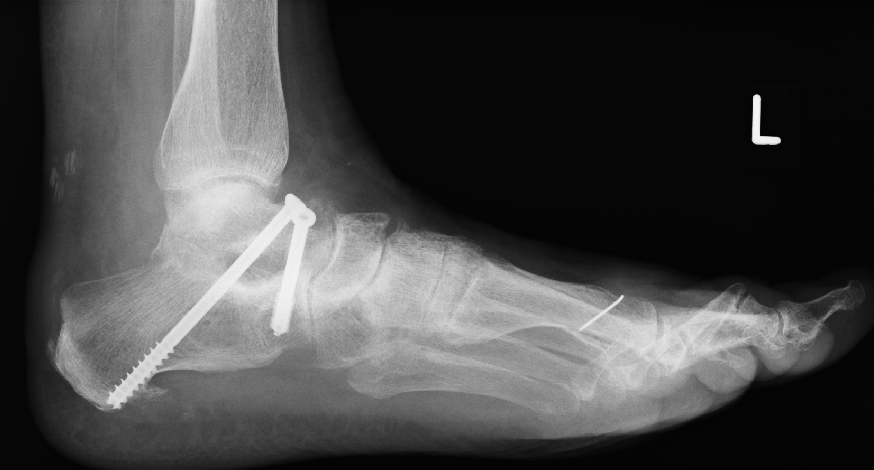

Aufrichtung durch Stabilisierung

Die Stabilisierung des unteren Sprunggelenkes (Arthrodese) ist eine effektive Methode zur Korrektur des fortgeschrittenen Knick-/Senkfußes, wenn hier bereits als Folge der Fehlstellung Arthrose aufgetreten ist. Dieser Eingriff wird ebenfalls oft mit weiteren Maßnahmen der Fußinnenseite kombiniert. Einige Monate nach der Operation ist in der Regel von außen am Gangbild nicht zu erkennen, dass ein Fußgelenk versteift wurde.

Minimal invasive Fußchirurgie

Die Durchtrennung der Ferse erfolgt über einen kleinen Hautschnitt von ca. 2-3mm. Zur Stabilisierung ist eine Schraube notwendig, die über einen weiteren Schnitt von ca. 7-8mm erfolgt.